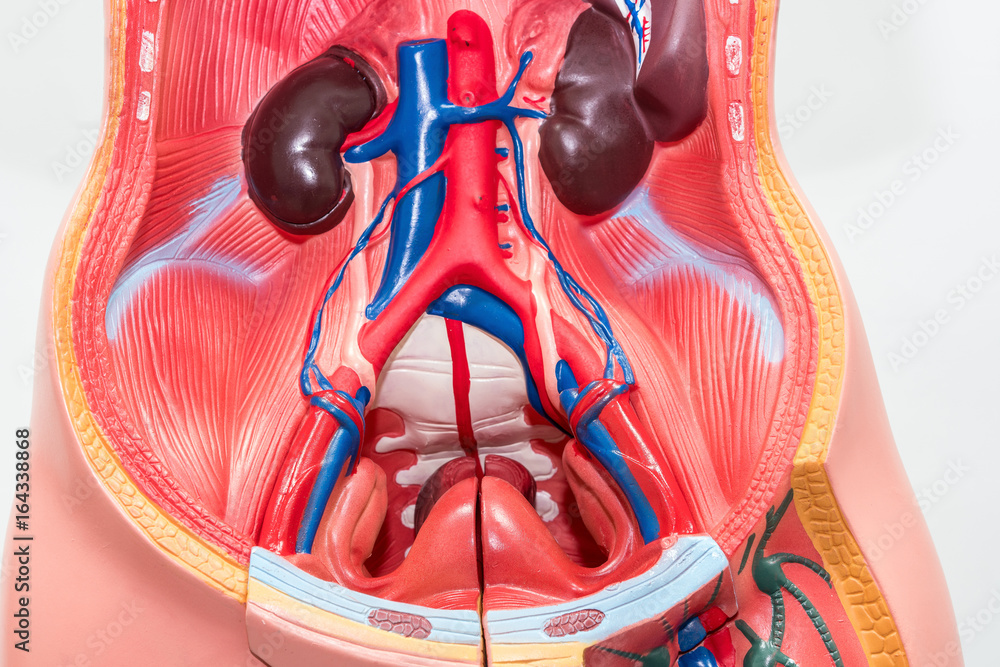

Боль в малом тазу у женщин: Причины и подходы к лечению